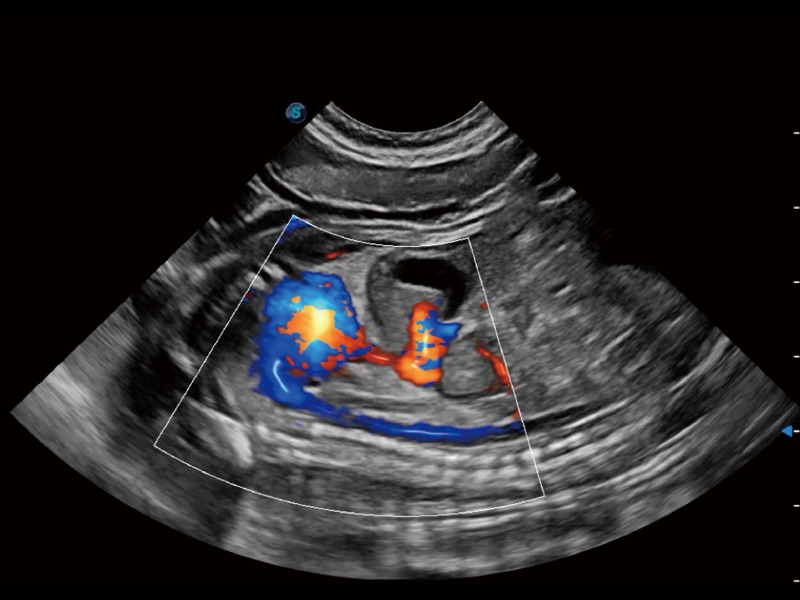

(犬)肾脏显微血流

(犬)左室长轴血流

(犬)胎儿主动脉弓立体血流